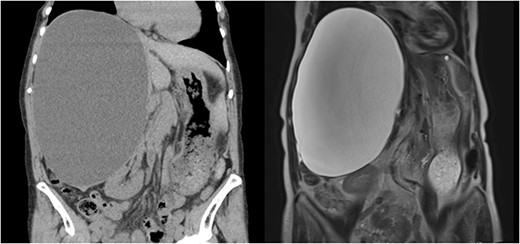

A 76-year-old woman, with an asymptomatic simple hepatic cyst in the right lobe of the liver, was closely monitored via magnetic resonance imaging (MRI) for 4 years. Only a slow annual increase in size was observed on MRI. One month before her surgery, the patient presented with abdominal distention. Blood examination for tumor markers, such as carcinoembryonic antigen and carbohydrate antigen 19-9, was within normal limits. Her biliary enzymes were slightly elevated (alkaline phosphatase of 151 U/l and γ-glutamyl trans peptidase of 61 U/l). A 13 × 17 × 24 cm hepatic cyst was observed in both computed tomography (CT) and MRI. Moreover, T2-weighted MRI revealed diffused high-signal intensity, without any tumor-like lesions such as filling defects or nodules (Fig. 1). Therefore, the diagnosis of a simple hepatic cyst was made, and she was recommended to undergo a laparoscopic deroofing for her symptomatic state.

A 13 × 17 × 24 cm hepatic cyst in the right lobe is observed in both CT and MRI.